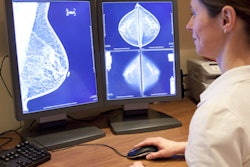

Breast ultrasound is considered a valuable adjunct to mammography for diagnosing breast cancer, and its use has increased in recent years, Park and colleagues noted.

"Ultrasound is an easily available, inexpensive imaging tool, without the accompanying risk of radiation, and therefore there has been an expansion in indications for the use of breast ultrasound, including serving as an adjunctive screening tool to mammography, for preoperative staging, follow-up after cancer treatment, and interventional diagnosis," the researchers wrote.

But the diagnostic accuracy of the modality is tied to the skill and experience of the operator. Research has demonstrated that using CAD with ultrasound can mitigate user variability, yet there have been few studies examining how CAD affects the diagnostic performance of readers with differing breast imaging experience (Medicine, January 2019, Vol. 98:3, p. e14146).

Park's team investigated the value of a CAD program applied to diagnostic breast ultrasound based on operator experience. The group used ultrasound images of 100 breast masses acquired from 92 women between May and June 2015; three less-experienced (first-year fellowship trainees) and two experienced (eight to 10 years) breast imaging radiologists analyzed the ultrasound features of the breast masses without and with CAD, using BI-RADS categories.